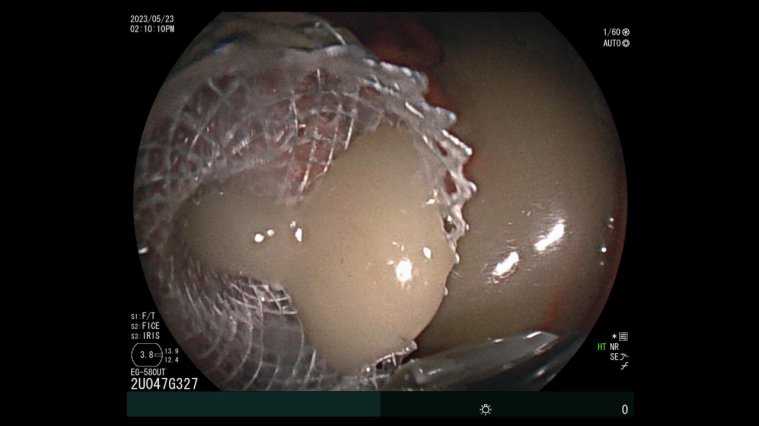

近日我院嘉定院区消化内科胡冰主任、吴军副主任带领的团队,成功为一名胰腺假性囊肿患者,实施精准囊肿引流并放置金属支架。这也是我院首例经超声内镜下电切引流支架置入术(HOT AXIOS技术)。 胡冰教授团队经超声内镜仔细评估后,发现患者囊腔内坏死组织多,传统引流方式效果可能不佳。经过缜密的术前讨论,最终决定采用最新超声内镜下微创电切引流支架置入术(HOT AXIOS技术)。 吴军医生指出: 相较于外科手术和经皮穿刺引流,超声内镜引导下胰腺假性囊肿引流术更加直接方便,相当于在囊肿和胃腔之间搭一个“桥”,把囊肿里面的液体引流到胃腔,一段时间后囊肿就会消失。急性胰腺炎后出现胰腺假性囊肿

本例患者采用的新型胰腺假性囊肿引流技术